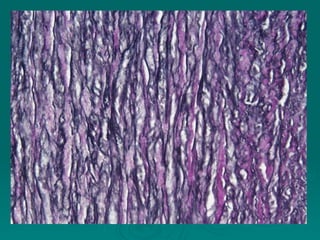

Connective tissues support and bind together other structures throughout the body. They are composed of connective tissue cells, ground substance, and fibers. Connective tissues have few cells separated by an abundant intercellular substance containing fibers. Their main functions are to bind tissues, provide mechanical support, store fat and minerals, allow for metabolite exchange, and aid in repair and healing. Connective tissues are classified as connective tissue proper, which includes loose and dense connective tissues, and specialized connective tissues like cartilage, bone, and blood.